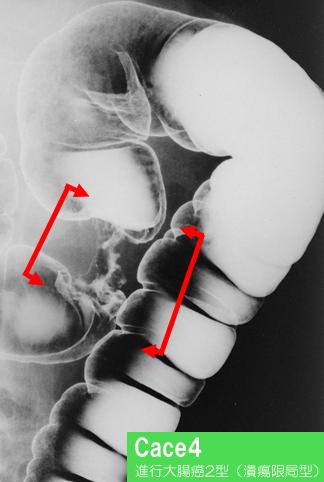

Eight cases of typical advanced colorectal cancer in which each type of radiological images were respectively compared with surgical specimens.

[Image-ID:11911]

악성 상피성종양/선암

대장/횡행

X-P

2형(궤양국한형)/

35~40

s(a)